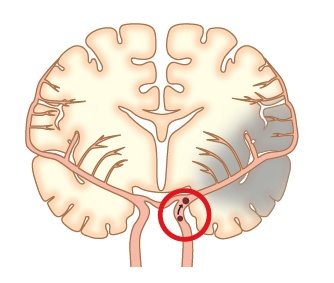

1)ラクナ梗塞

脳の中の細い血管が1本詰まることにより起きる脳梗塞です。脳が壊死する範囲は比較的狭く、軽症で済むことが多く、命に関わることはありません。しかし詰まる場所によっては重い半身麻痺などの後遺症が残ることもあります。治療は点滴と飲み薬が主体で手術が行われることはありません。この脳梗塞になる方はたいてい、高血圧症をもっています。